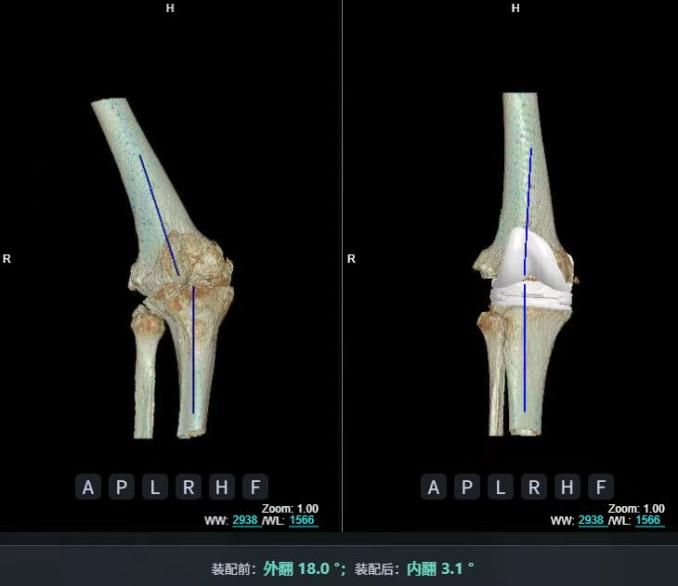

4.2 APTT-HTO脛骨高位截骨術(shù)

2025年7月,貴州醫(yī)科大學(xué)附屬醫(yī)院骨科團(tuán)隊(duì)原創(chuàng)研發(fā)的腘肌前結(jié)節(jié)中脛骨高位截骨保膝術(shù)(Anterior Popliteus Transtibial Tuberosity-High Tibial Osteotomy, APTT-HTO)及其提出的脛骨結(jié)節(jié)分區(qū)與腘肌保護(hù)理論,登上了國(guó)際頂尖學(xué)術(shù)舞臺(tái)。該成果在全球最具影響力的專業(yè)會(huì)議之一——日本骨科協(xié)會(huì)第98屆年會(huì)上進(jìn)行了兩次學(xué)術(shù)發(fā)言。[8]

該手術(shù)具有經(jīng)皮微創(chuàng)、保留原生膝關(guān)節(jié)結(jié)構(gòu)、符合階梯治療原則等優(yōu)勢(shì),通過調(diào)整下肢力線可促進(jìn)部分軟骨再生,術(shù)后關(guān)節(jié)功能接近正常(如下蹲、爬山),患者還能從事中重體力勞動(dòng)。相比其他術(shù)式,其有效規(guī)避了髕骨低位、血管損傷、合頁骨折等潛在并發(fā)癥。

目前,APTT-HTO技術(shù)已成功應(yīng)用于千余名患者,幫助保留自身膝關(guān)節(jié)。此類保膝手術(shù)適用于單間室膝關(guān)節(jié)炎患者(如 “羅圈腿”),核心是通過調(diào)整力線糾正畸形,減輕磨損間室壓力、發(fā)揮健康間室作用,延長(zhǎng)膝關(guān)節(jié)壽命。若出現(xiàn)膝關(guān)節(jié)疼痛、保守治療無效且X線顯示關(guān)節(jié)間隙部分狹窄,建議及時(shí)就醫(yī)評(píng)估是否適合手術(shù)。